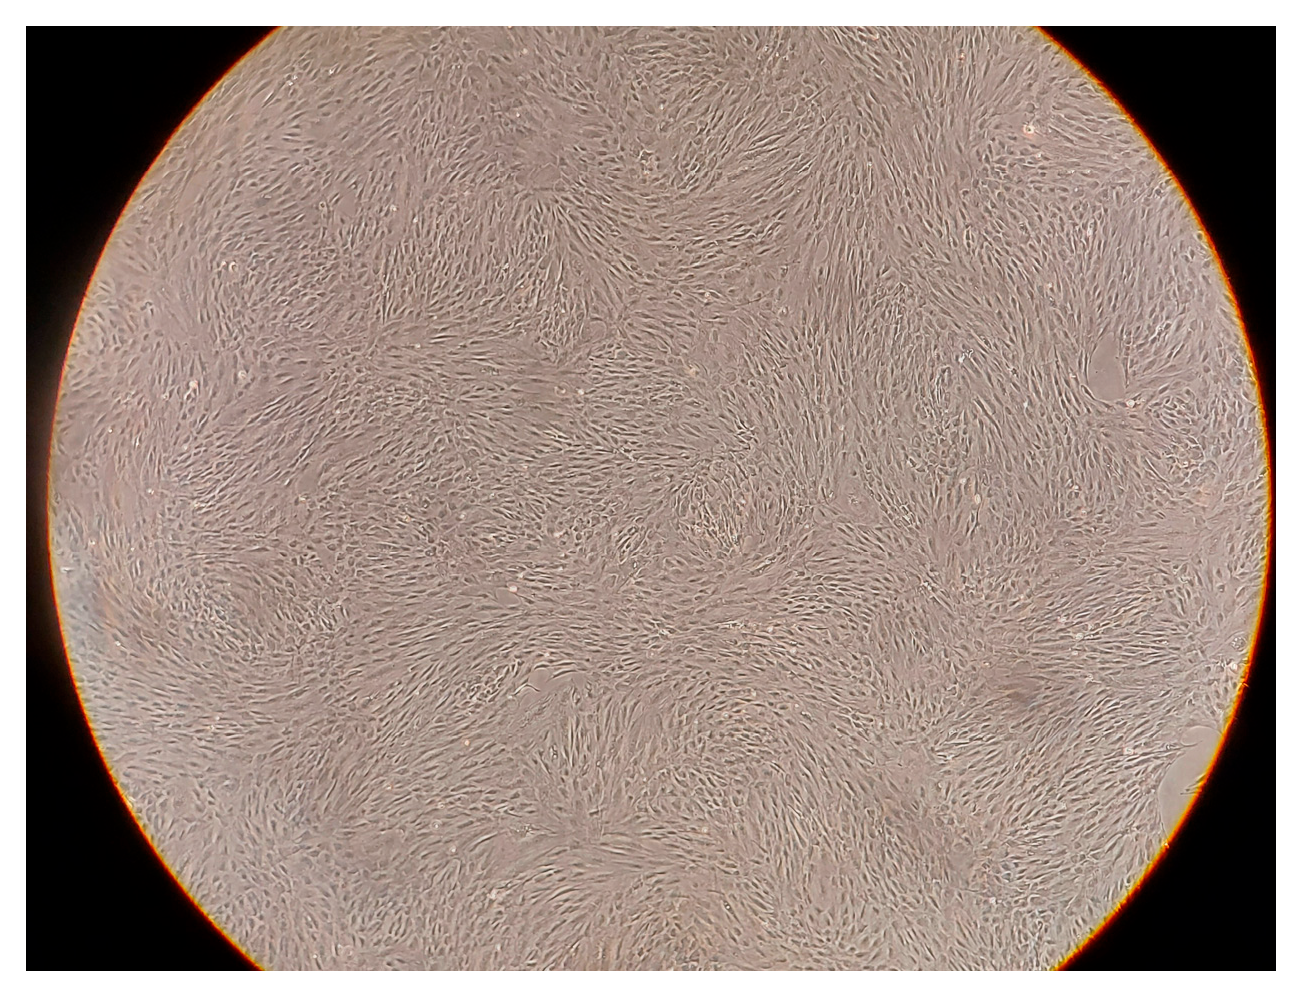

4.2. Stem Cells